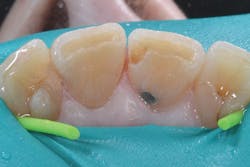

A 20-year-old female patient presented for a core buildup on tooth No. 4 following unremarkable root canal therapy. The tooth was isolated with a Palodent Plus Sectional Matrix System, and Prime&Bond Elect Universal Adhesive (Dentsply Sirona) was applied per manufacturer’s directions (figure 2). An initial 1 mm layer of SureFil SDR flow+ universal shade was placed over the gutta percha and light cured.